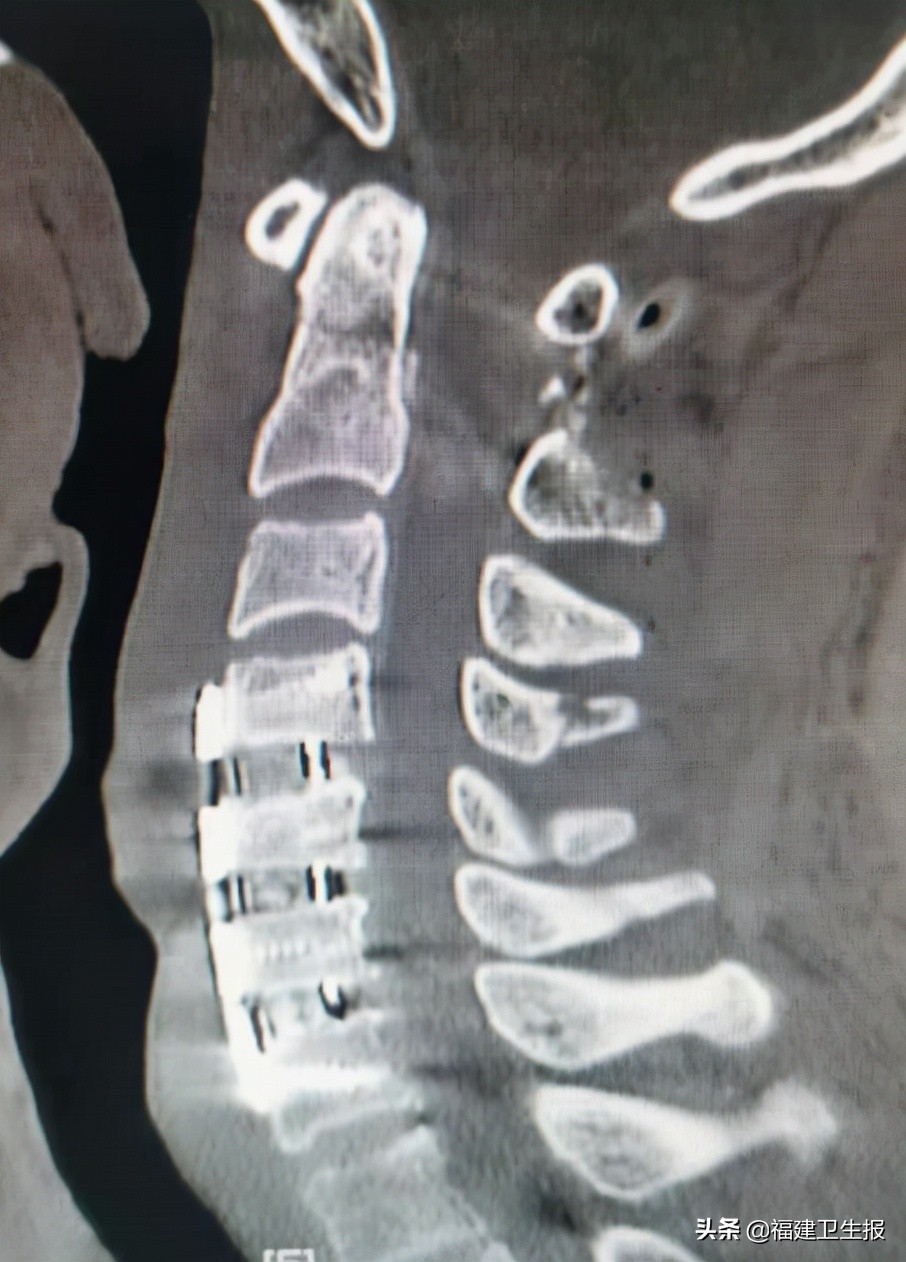

术后患者很快恢复清醒,四肢开始活动。术后第一天患者双上肢可自行举起,双手握力开始恢复。术后第5天患者各引流管均拔除,佩戴颈托自行下地步行良好,双上肢肌力恢复正常,下肢肌力正常,各项生活可自理,复查颈椎X线片及颈椎CT见枢椎齿状突骨折及寰椎复位良好,内固定精准在位。

▲CT